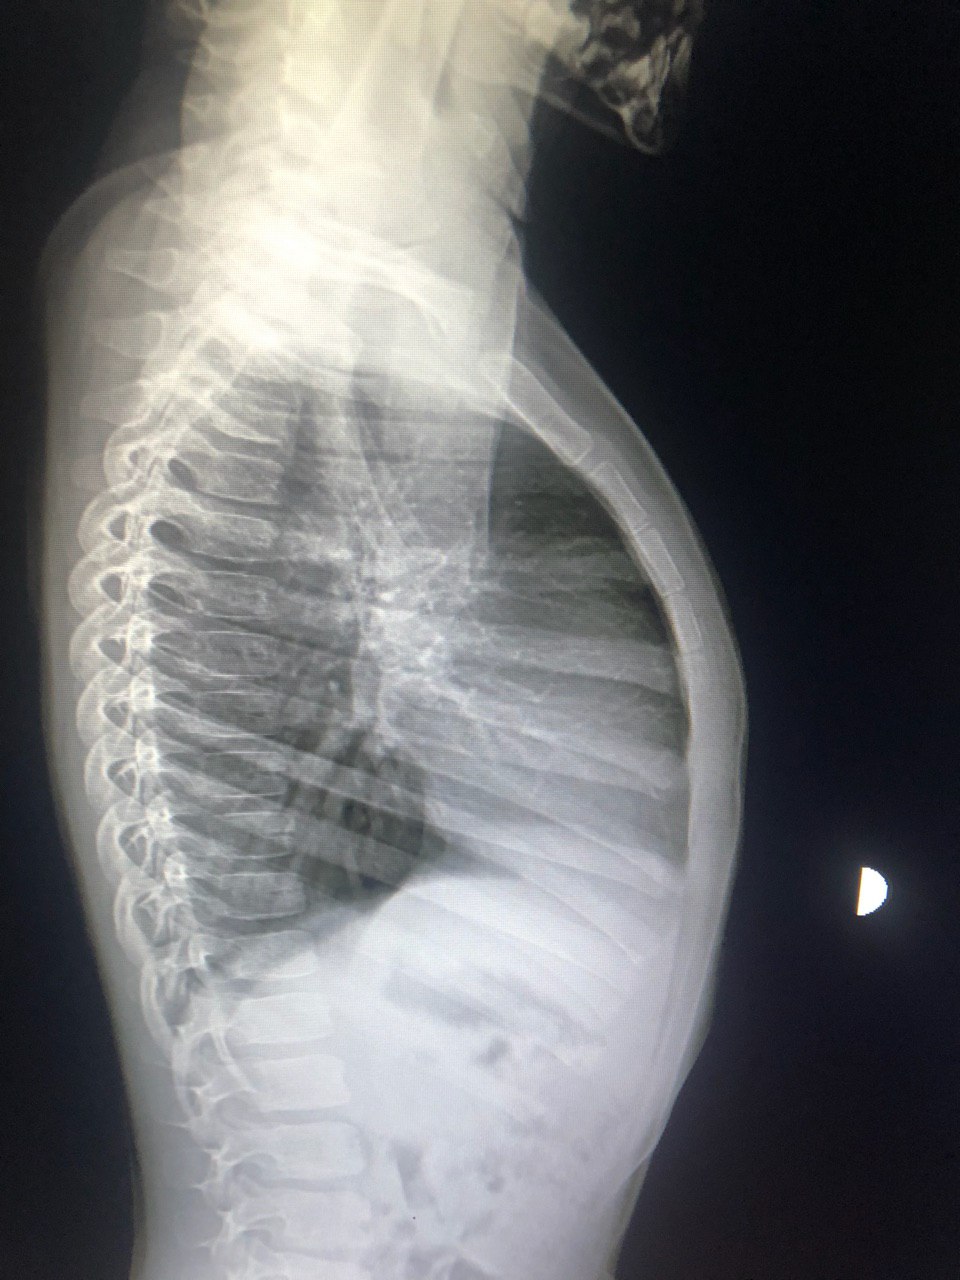

Уважаемые коллеги у ребенка pectus carinatum, есть ли?

Есть асимметричная воронкообразная деформация. Прямой покажите пожалуйста.

То есть можна описать так?

Костной патологии не выявлено.

Там дефект в хрящевой части ребер.

Если вообще он там есть...